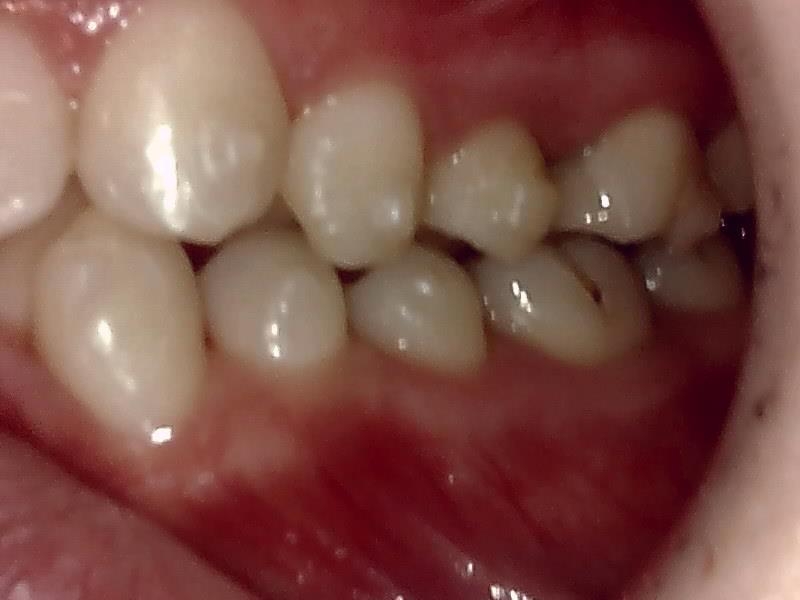

左側

右側